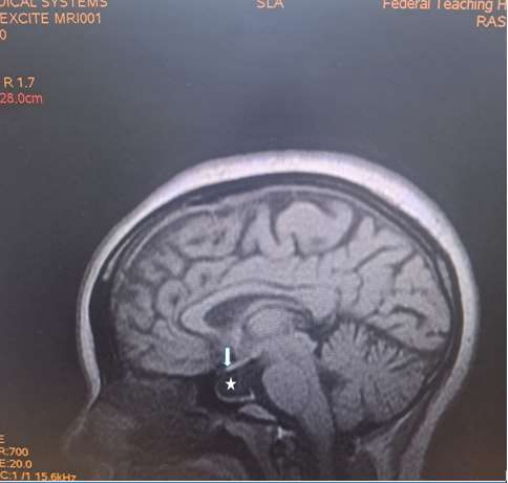

Magnetic Resonance Imaging (MRI) revealed expansion of the sella with a well-defined fairly rounded lesion measuring 15 X 14 X 15mm (width X AP X H). It is hypointense on T1W, hyperintense on T2W and suppressed on FLAIR sequence. Rim enhancement is seen post contrast. The mass is inseparable from the optic chiasma suggestive of compression.

Figure 4: Sagittal T1W image of the brain showing a hypointense rounded intrasellar mass lesion (white asterisk) with obliteration of the optic chiasma (white arrow).

Clinically, majority of lesions less than 3mm are asymptomatic6. However, when large, the typical symptoms include headache, visual loss and endocrinologic dysfunction7,8. The case presented had recurrent headache, poor vision, amenorrhoea, loss of libido and occasional galactorrhea. No heat or cold intolerance. No convulsion or loss of consciousness. The headache seen is due to raised intracranial pressure from the mass which is non-specific. It may also be due to cyst wall infarction, haemorrhage or leakage of inflammatory contents14. The poor vision seen is due to compression of the optic chiasma by the cyst, while the amenorrhoea, loss of libido and galactorrhea are the result of the endocrine dysfunction usually seen in the disease [16].

Rathke’s cyst is visualised on magnetic resonance imaging as a lesion located in the intermediate lobe of the pituitary. Its largest diameter usually does not exceed 20 mm9. The cyst may have varying intensity against the cerebrospinal fluid, although it is more often hypointense in T1-weighted images and hyperintense in T2-weighted images. RCC image captured on MRI is described as “an egg in a shell [9]. The enhancement of the cyst wall following contrast administration suggests inflammation or metaplasia [11].

Due to its high soft tissue resolution, Magnetic Resonance Imaging (MRI) is the primary diagnostic technique for RCC9. It also determines the cystic content and fluidity of the cyst which is useful in planning for subsequent patient’s management10. Fifty percent are hyperintense on T1W (due to high protein content) while 50% are hypointense. On T2W, 70% are hyperintense, 30% iso or hypointense and 20% have hypointense rim. T1W Post contrast images usually show no enhancement. However, a thin enhancing rim may be seen when cyst wall infection is present [19-20]. The case presented revealed expansion of the sella with a well-defined fairly rounded lesion measuring 15 X 14 X 15mm (width X AP X H). It is hypointense on T1W, hyperintense on T2W and suppressed on FLAIR sequence. Rim enhancement is seen post contrast. The mass is inseparable from the optic chiasma suggestive of compression. The appearance of the cyst confirmed no haemorrhage or debris within the cyst. However, the rim enhancement suggest inflammation of the cyst as explained in the text. The finding of optic chiasma compression may explain the visual impairment and the bitemporal hemianopia seen in the patient.